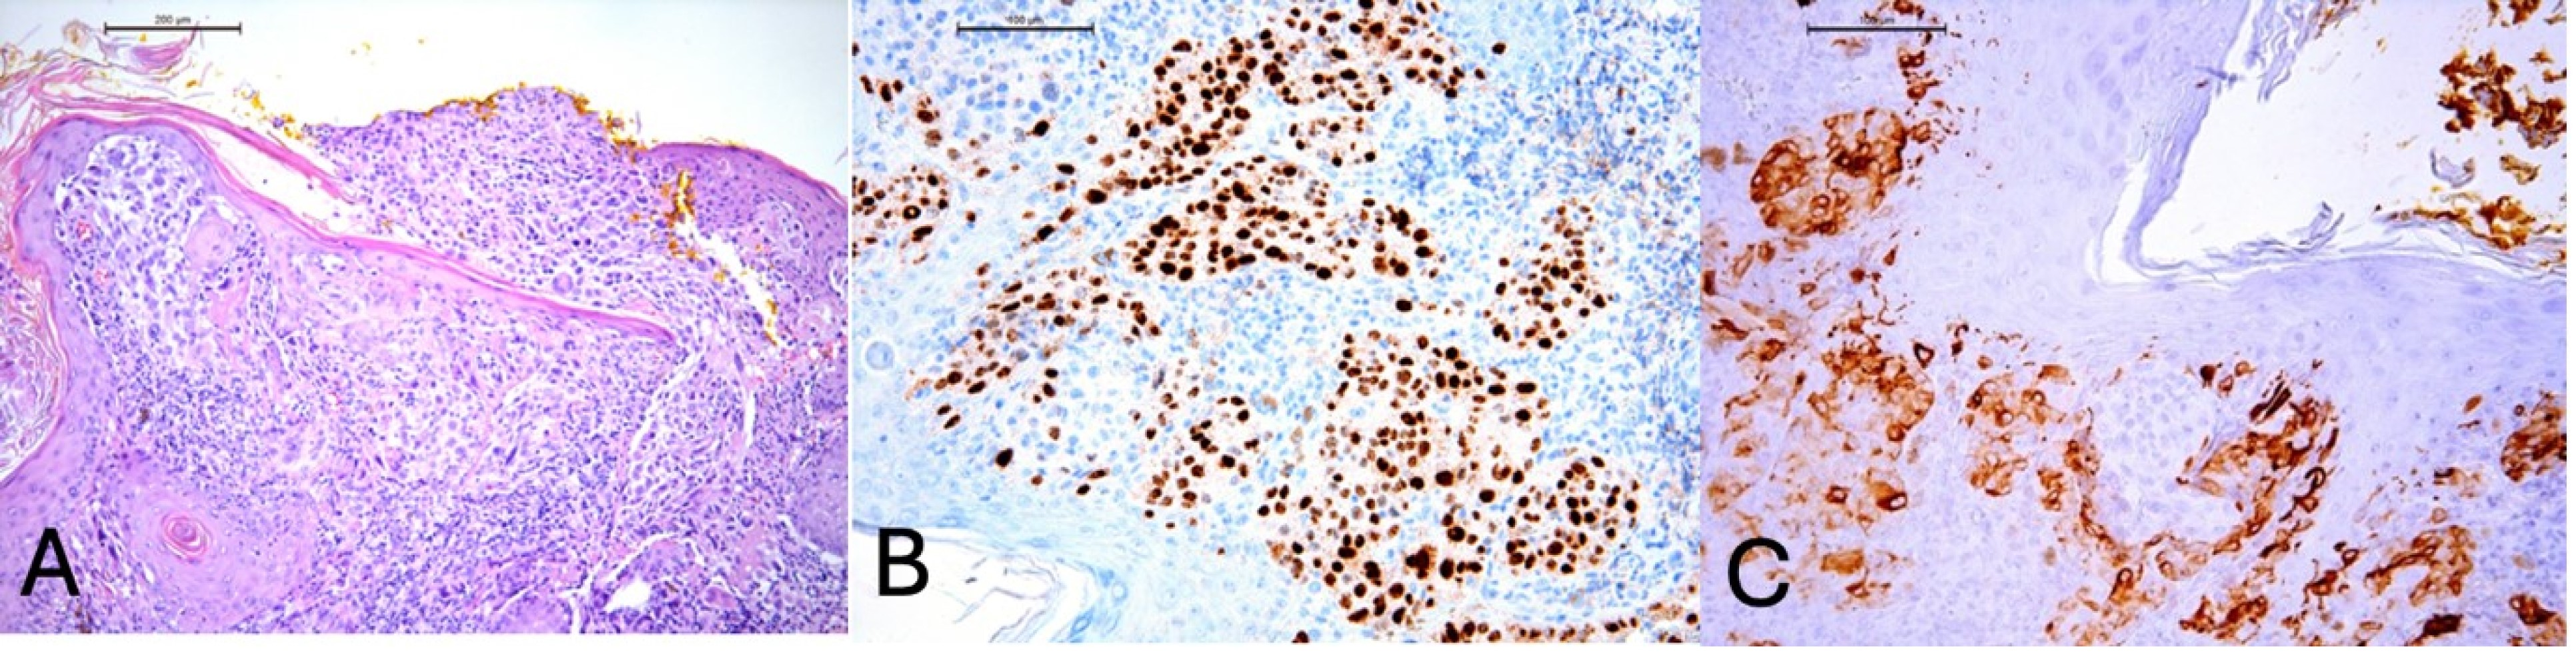

2. Case Description